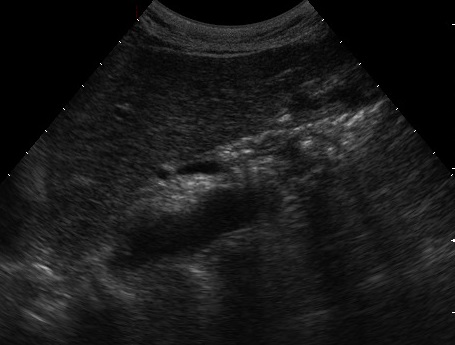

Image de pseudokyste d'une

pancreatite chronique tardive ( fleche rouge ) . Sa

contenue interieure est souvent 20UI et changement

de densite dans cas infection ou hemorragique |